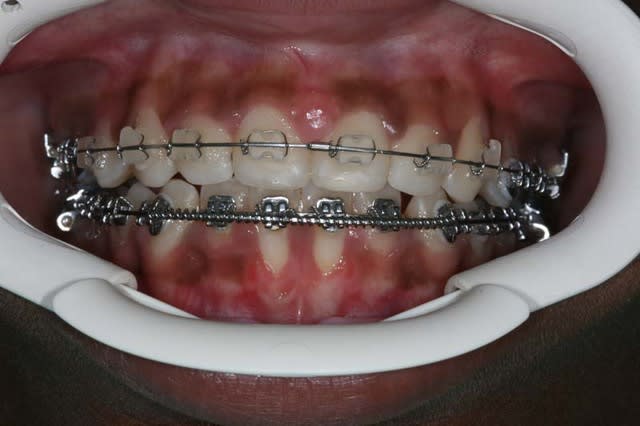

situation actuelle

avec l’accord des parents, qui ont été prévenus que le ttt. pouvait être interrompu pour raisons parodontales, j’ai commencé le ttt. en repoussant la greffe à la fin du ttt. si pas de Pbs.

@+ Bjc.

Actuel viclc9 - Eugenol